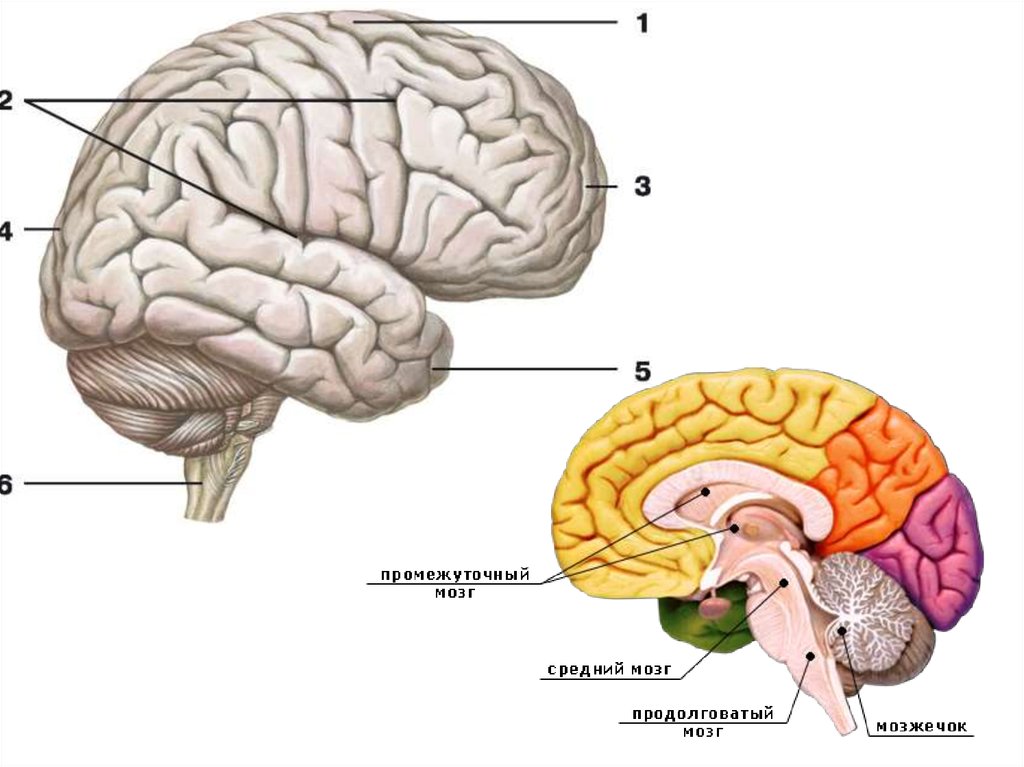

Анатомические снимки верхнелатеральной поверхности головного мозга